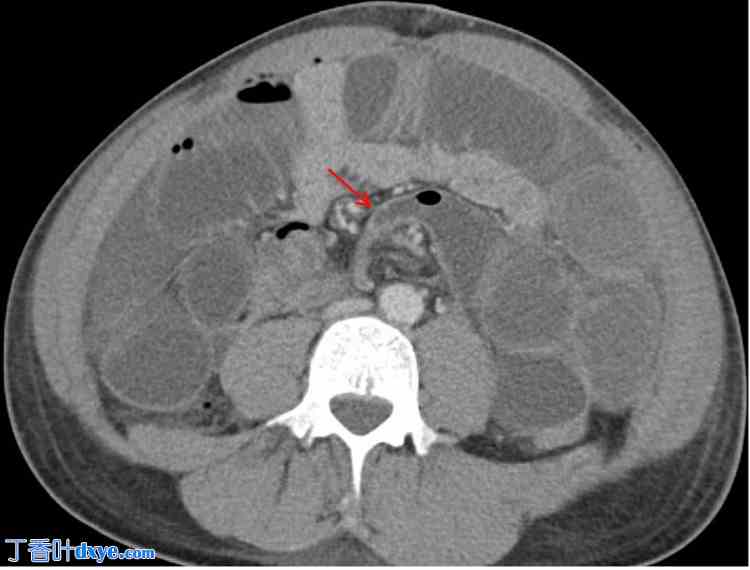

体格检查发现患者营养不良和间歇性腹胀。内镜检查和影像学检查等诊断评估证实回盲瓣和幽门管明显狭窄,并伴有纤维化狭窄和轻微活动性炎症(图1)。鉴于患者病情难治且对药物治疗反应不佳,医生认为有必要进行手术治疗。

图1. CT小肠造影(冠状位),患者胃部膨胀,幽门管狭窄(红色箭头),提示胃出口梗阻。